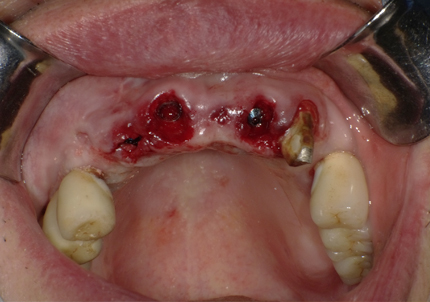

5.インプラント埋入(2021年6月)

※ 初期固定35N/cm確認する

6.二次手術

インプラント周囲の角化歯肉(付着歯肉:骨に固定されてる歯肉)の獲得を目的に歯肉弁を移動する